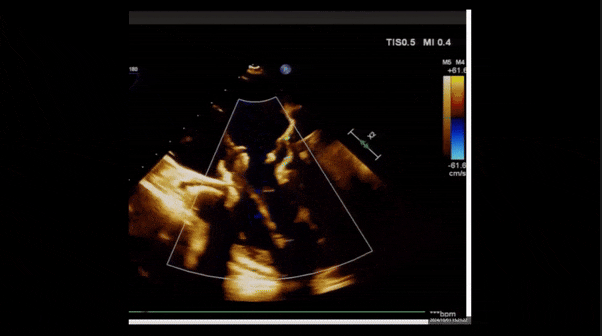

術(shù)后即刻返流

術(shù)后即刻返流三維

術(shù)后即刻經(jīng)食道超聲可見,三尖瓣假體瓣膜位置合適,牛心包瓣葉運(yùn)動狀態(tài)良好,開閉正常,瓣周及瓣葉對合緣處未見明顯返流,心電圖及心包狀態(tài)較術(shù)前無明顯變化。

術(shù)前術(shù)后返流情況對比